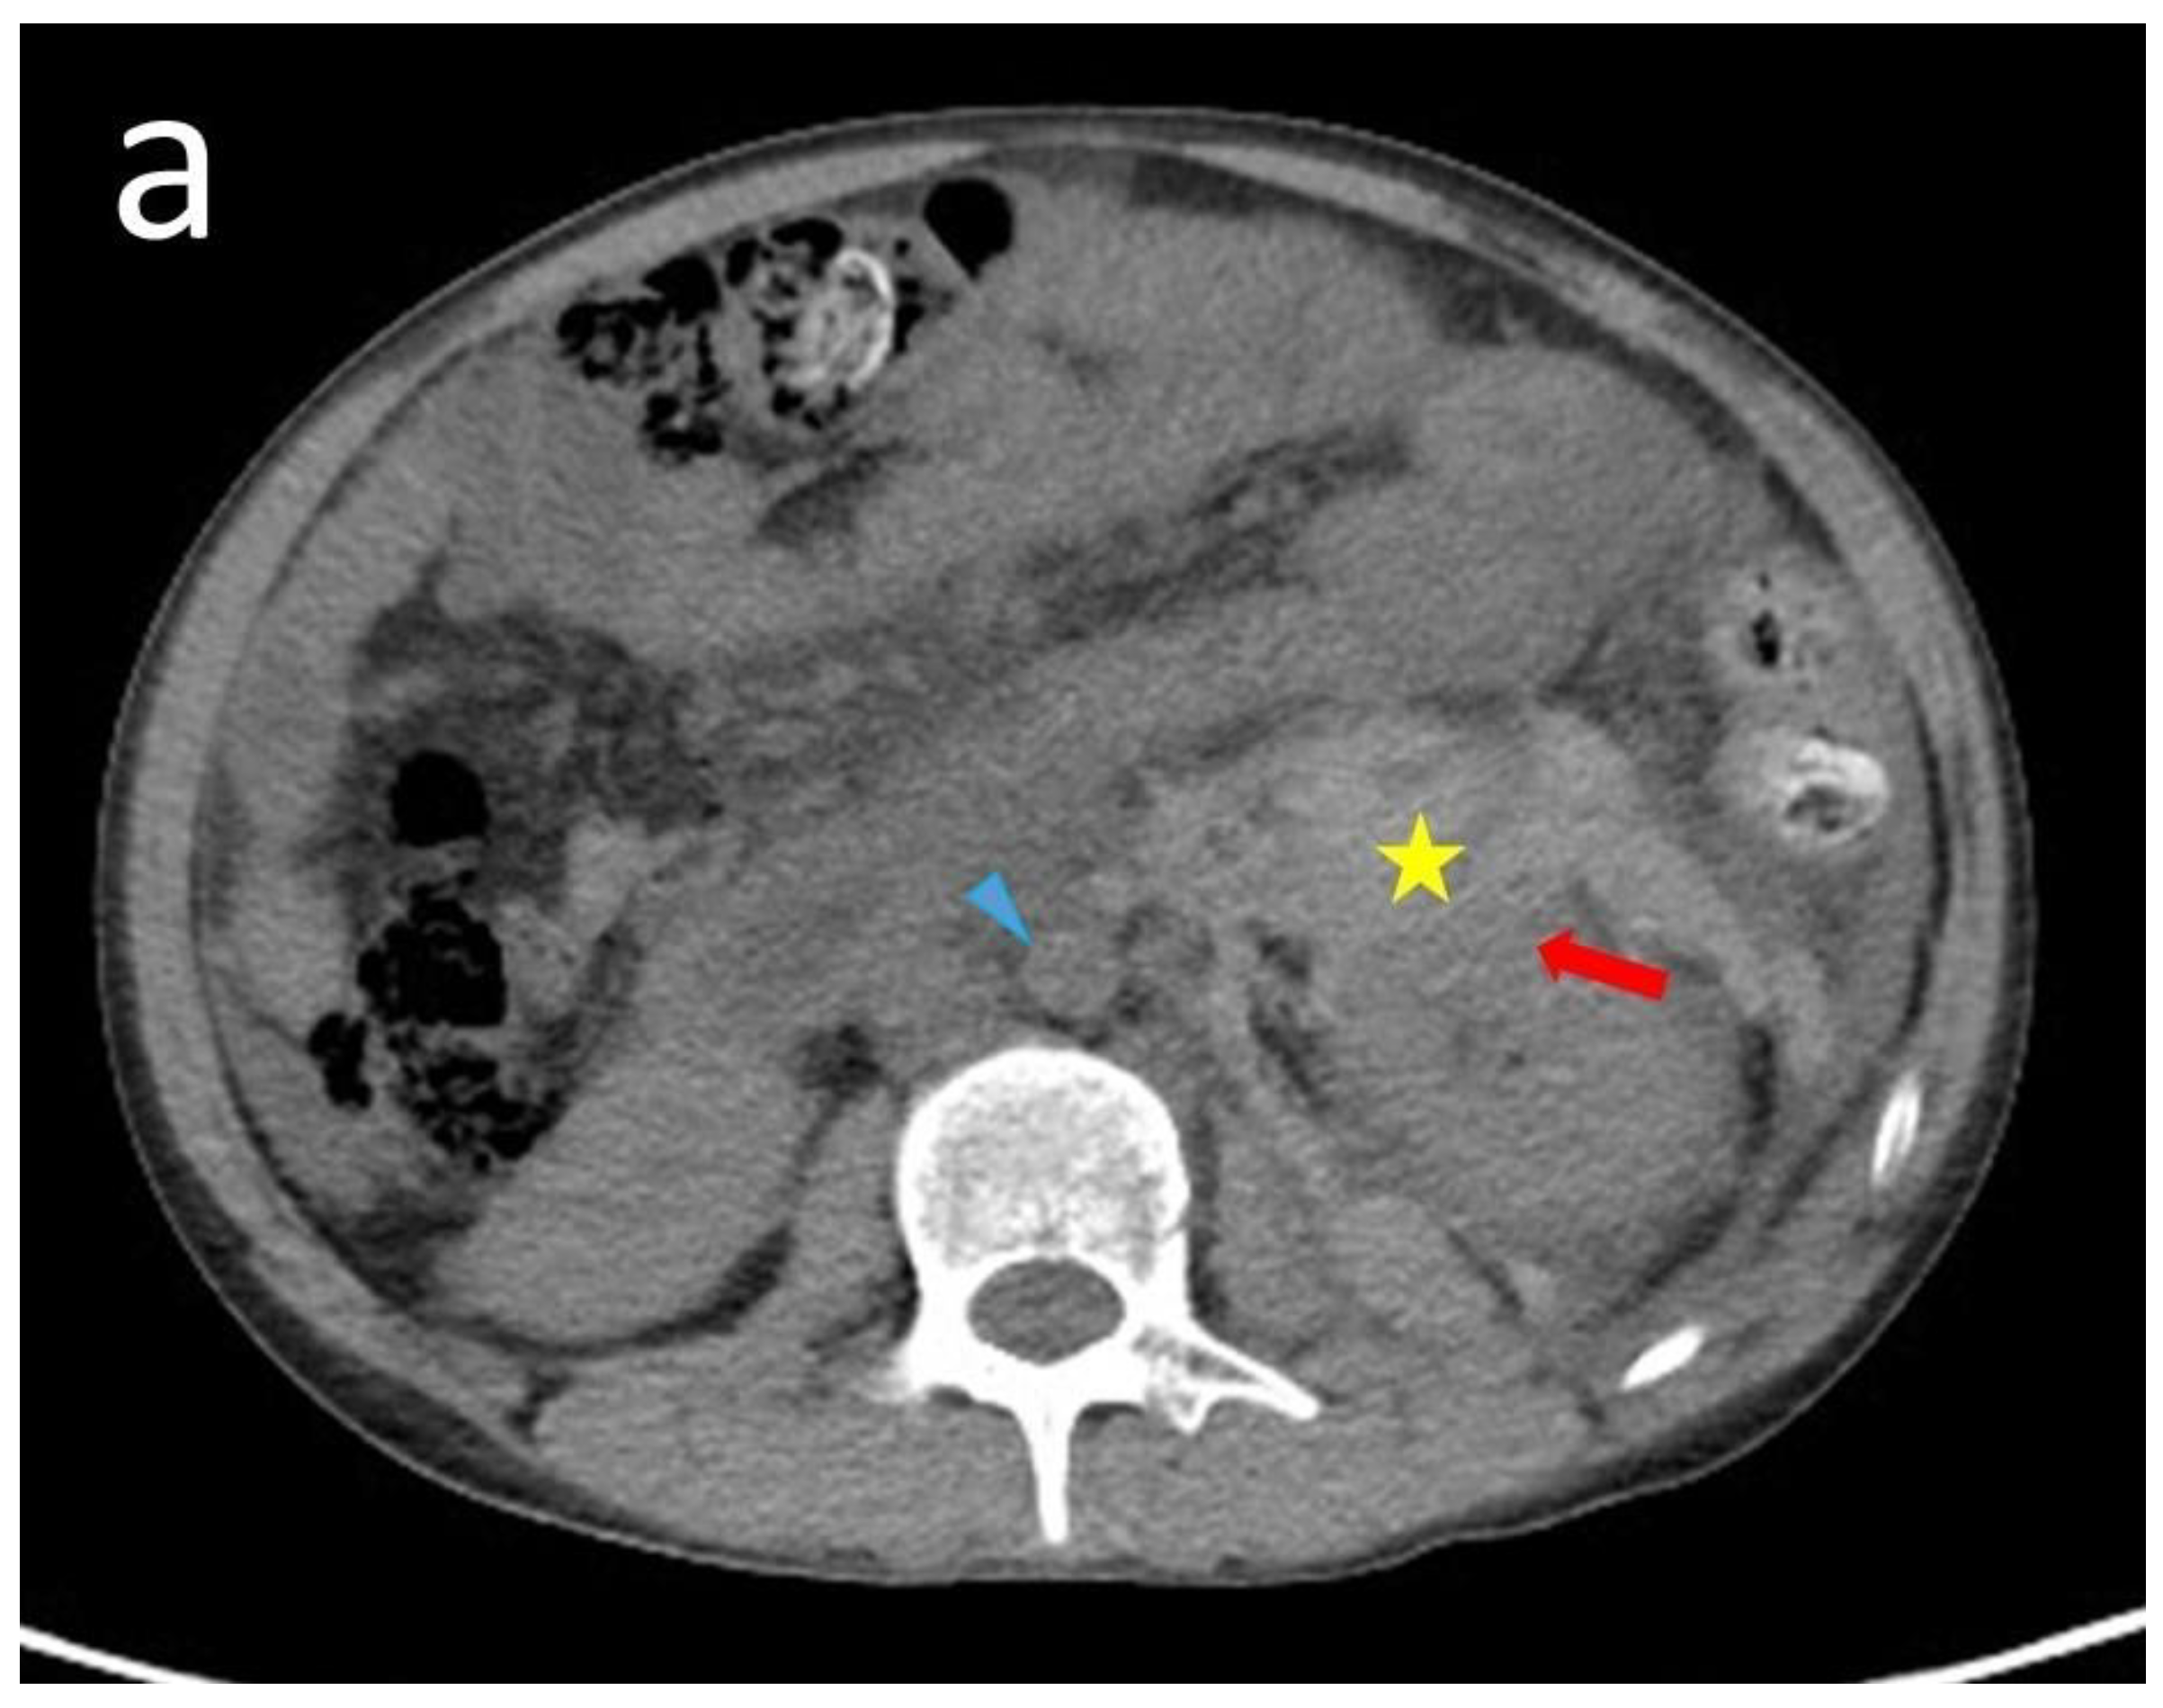

| 13 | Our case | 18 | Male | 12 | Flank pain Anemia(Hb: 6.7 g/dL) | Normal | Normal | CT | Angiodysplasia of the left renal artery & branch of IMA | N/A | Anti-dsDNA antibody Lupus anti-coagulant Anti-cardiolipin IgM | Embolization Steroid | N/A | Alive |